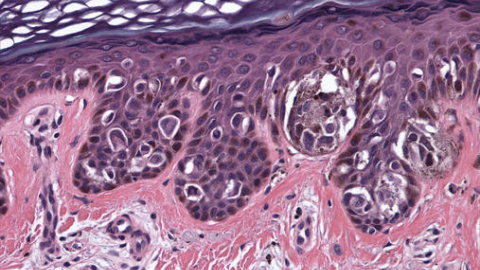

MADRID.- Un equipo internacional dirigido por investigadores españoles ha descubierto un nuevo tipo de fármaco con un potente efecto antitumoral en modelos animales de cáncer colorrectal y melanoma. Varias compañías se han interesado en el compuesto para estudiar sus posibles aplicaciones como terapia antitumoral en humanos.

Según describen en el estudio publicado en Cancer Cell, los científicos han identificado una molécula, DEL-22379, que logra causar la muerte de las células tumorales, según explica el director del estudio, Piero Crespo, investigador del CSIC en el Instituto de Biomedicina y Biotecnología y de Cantabria.